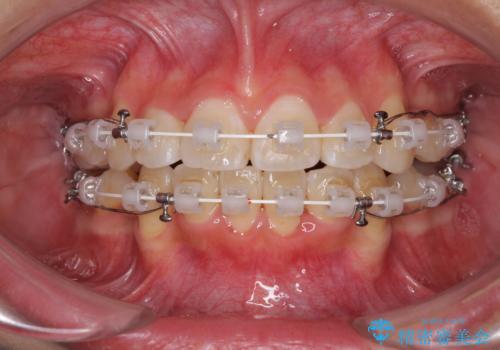

- 審美装置

- 2年3ヶ月

- 10-30回